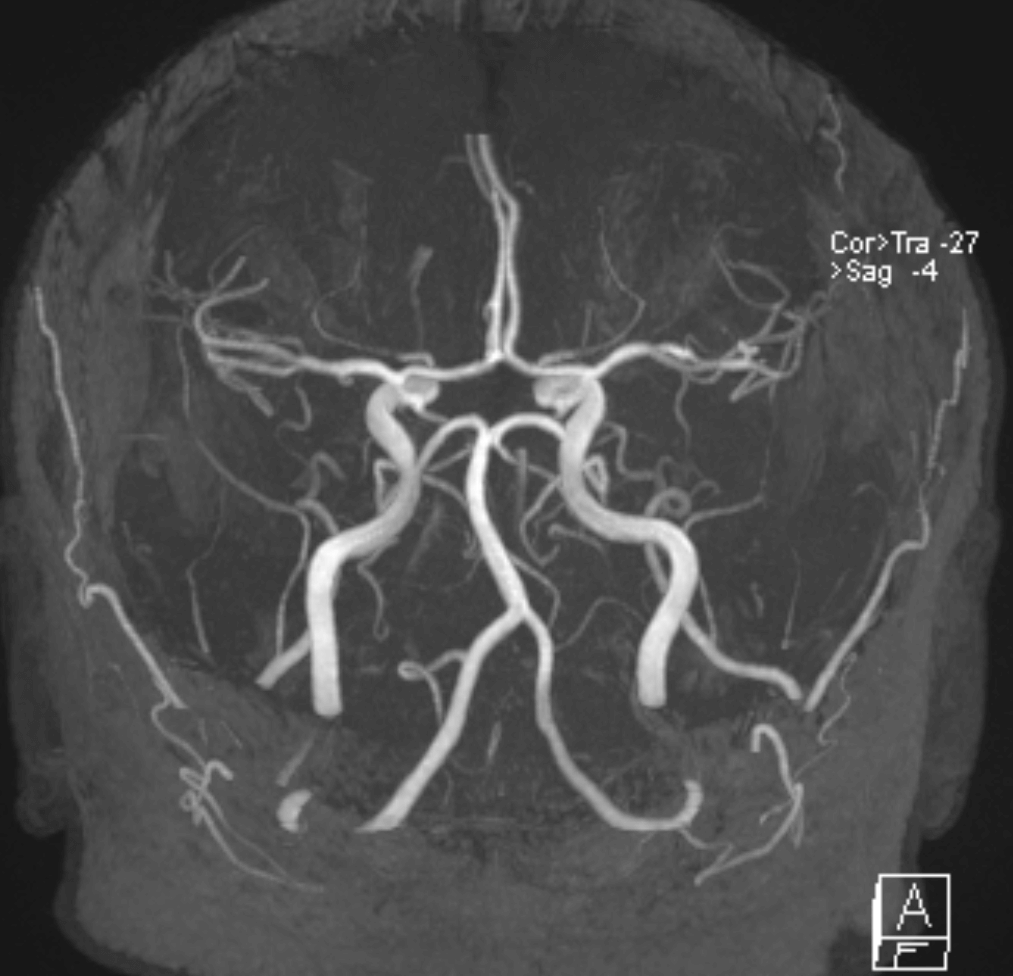

Gefäßdarstellung

Zur Darstellung der Gefäße im Kopf wurde die Technik der MR-Angiographie (kurz MRA, MR-Gefäßdarstellung) entwickelt. In dieser Technik können sowohl die blutzuführenden Gefäße (Arterien) als auch die blutableitenden Gefäße (Venen) dargestellt werden. Die Darstellung der Arterien wird vor allem bei Schlaganfällen oder Hirnblutungen benötigt, oder beispielsweise zur Darstellung von Aneurysmen (=Gefäßwandaussackungen). Die Darstellung der Venen erfolgt vor allem bei einem Verdacht auf eine Gerinnselbildung (sogenannte Sinus- oder Venenthrombose).